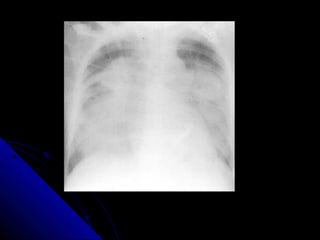

CCHHFF

CCaarrddiioommeeggaallllyy..

UUppppeerr lloobbee ddiivveerrssiioonn..

KKeerrlleeyy--BBlliinneess..

PPlleeuurraall eeffffuussiioonn..

BBaattwwiinngg eeddeemmaa..